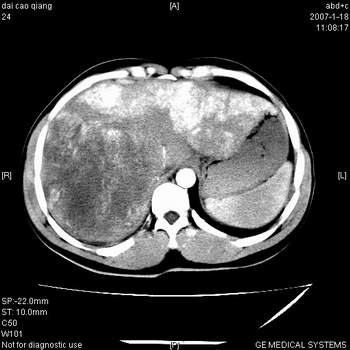

符合巨块型肝癌表现:

1、平扫低密度,增强后表现为快进快出。

2、动脉期可见迂曲的动脉供血血管

3、并可见门静脉右支癌栓形成

4、可见假包膜

5、腹主动脉旁结节影,考虑肿大淋巴结。

肝右叶巨大不均匀低密度肿块,前缘有假包膜,增强明显的呈快进快出表现,门脉右支有癌栓,病人虽然年轻但还是首先考虑肝右叶巨块形肝癌,病人血象高只能说有合并感染。不支持肝脓肿。